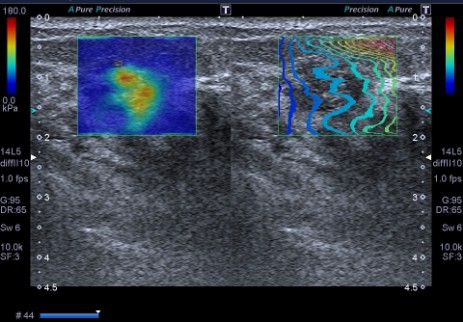

Elastografia SWE piersi (Shear Wave Elastography)

• Zasada działania: W przeciwieństwie do tradycyjnej elastografii (SE), SWE nie wymaga uciskania tkanki głowicą. Wykorzystuje ona impuls akustyczny do generowania fali poprzecznej, co zapewnia pełną obiektywizację i pomiary ilościowe w kPa lub m/s.

• Interpretacja: Twardsze tkanki (nowotwory) są wyświetlane na mapie kolorów inaczej niż tkanki miękkie (zmiany łagodne, torbiele).